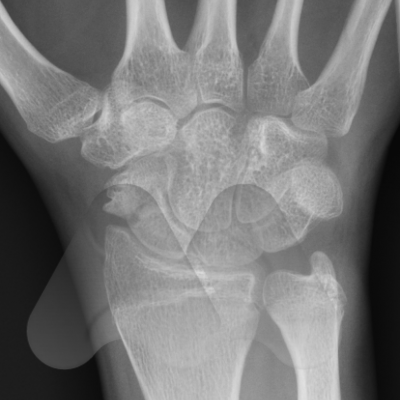

The Scaphoid is one of the eight carpal bones that make up the wrist. It is the commonest carpal bone to be fractured and is more common in young men. The injury occurs often from a fall onto an outstretched hand, sports related injury or a sudden torque injury from power tools. Scaphoid fractures tend to cause swelling and pain on the radial (thumb) side of the wrist and can often be overlooked as a wrist sprain. Despite seeking medical attention, there is a high rate of missed diagnoses due to many fractures not easily seen on initial X-Ray. The scaphoid has an unusual blood supply which can affect it’s healing. It is the key bone that stabilises the wrist and if a fracture is missed or does not heal, this can lead to collapse and arthritis in the wrist at an early age. If you have pain on the radial side of the wrist following an injury that continues for longer than a week, you should seek medical attention.

If initial X-Rays do not show the fracture but there is persistent pain and swelling in the radial side of the wrist, your doctor may ask you to have a CT or MRI scan to give more detailed imaging of the area. This can identify occult scaphoid fractures and the amount of displacement or other injured structures in the area such as distal radius fractures, scapholunate ligament injuries, trapezium fractures or other ligamentous injuries. This helps guide you and your doctor’s choice of treatment.